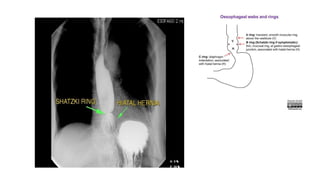

Schatzki rings

• A Schatzki ring, also called a Schatzki-Gary ring, is a symptomatic, narrow esophageal B-

ring occurring in the distal esophagus and usually associated with a hiatus hernia.

• The pathogenesis of the Schatzki ring is unclear with conflicting hypotheses that include

redundant pleats of mucosa, congenital abnormalities and modified peptic strictures.

Interestingly, there is a reduced incidence of Barrett esophagus in patients with a Schatzki ring.

• Depending on its luminal diameter, an esophageal B-ring may be symptomatic or asymptomatic 4:

• <13 mm: almost always symptomatic

• 13-20 mm: sometimes symptomatic

• >20 mm: rarely symptomatic

• When it is symptomatic, it is termed a "Schatzki ring" ref.

Schatzki rings • ASchatzki ring, also called a Schatzki-Gary ring, is a symptomatic, narrow esophageal B- ring occurring in the distal esophagus and usually associated with a hiatus hernia. • The pathogenesis of the Schatzki ring is unclear with conflicting hypotheses that include redundant pleats of mucosa, congenital abnormalities and modified peptic strictures. Interestingly, there is a reduced incidence of Barrett esophagus in patients with a Schatzki ring. • Depending on its luminal diameter, an esophageal B-ring may be symptomatic or asymptomatic 4: • <13 mm: almost always symptomatic • 13-20 mm: sometimes symptomatic • >20 mm: rarely symptomatic • When it is symptomatic, it is termed a "Schatzki ring" ref.